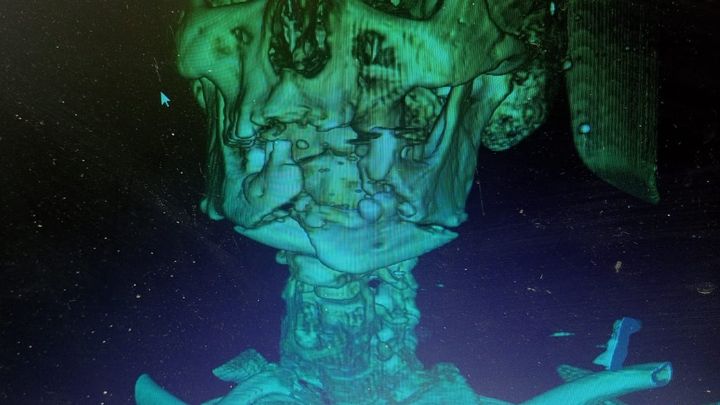

Our father was severely injured while attempting to secure an aid parcel from the GHF site! He suffered a bullet which fractured his jaw terribly. He is in a state of constant pain and requires complex surgeries to fully repair the damage. The doctors here did as much as they could for him, but he needs further treatment abroad. The medication required and the follow up monitoring are very expensive here. So we have amended this campaign to include the urgent need for his treatment on top of our basic survival needs. Please read below for the story of our journey over two years and give what you can. Thank you from the bottom of our hearts for your support.